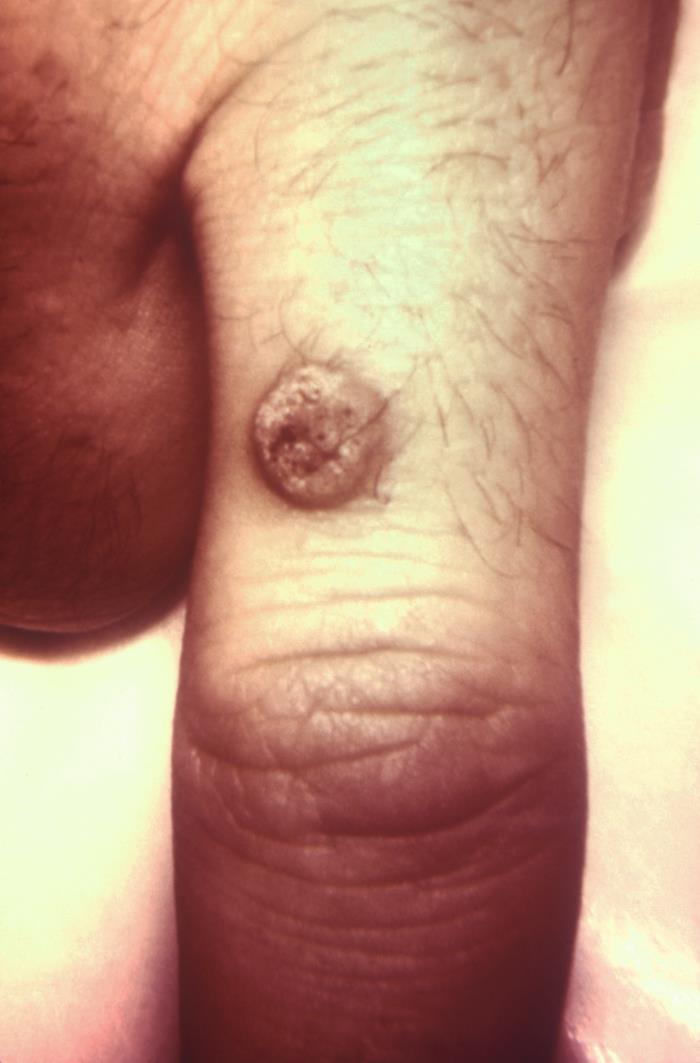

- Flat warts (verruca plana):

- Most commonly seen in children.

- Face [Fig 3], neck, chest, forearms, and legs flexor surfaces

Flat wart

Flat wart, also called verruca plana, in a middle-aged women.

Source: Wikimedia commons

Iffat Hassan, Taseer Bhat, Hinah Altaf, Farah Sameem, Qazi Masood